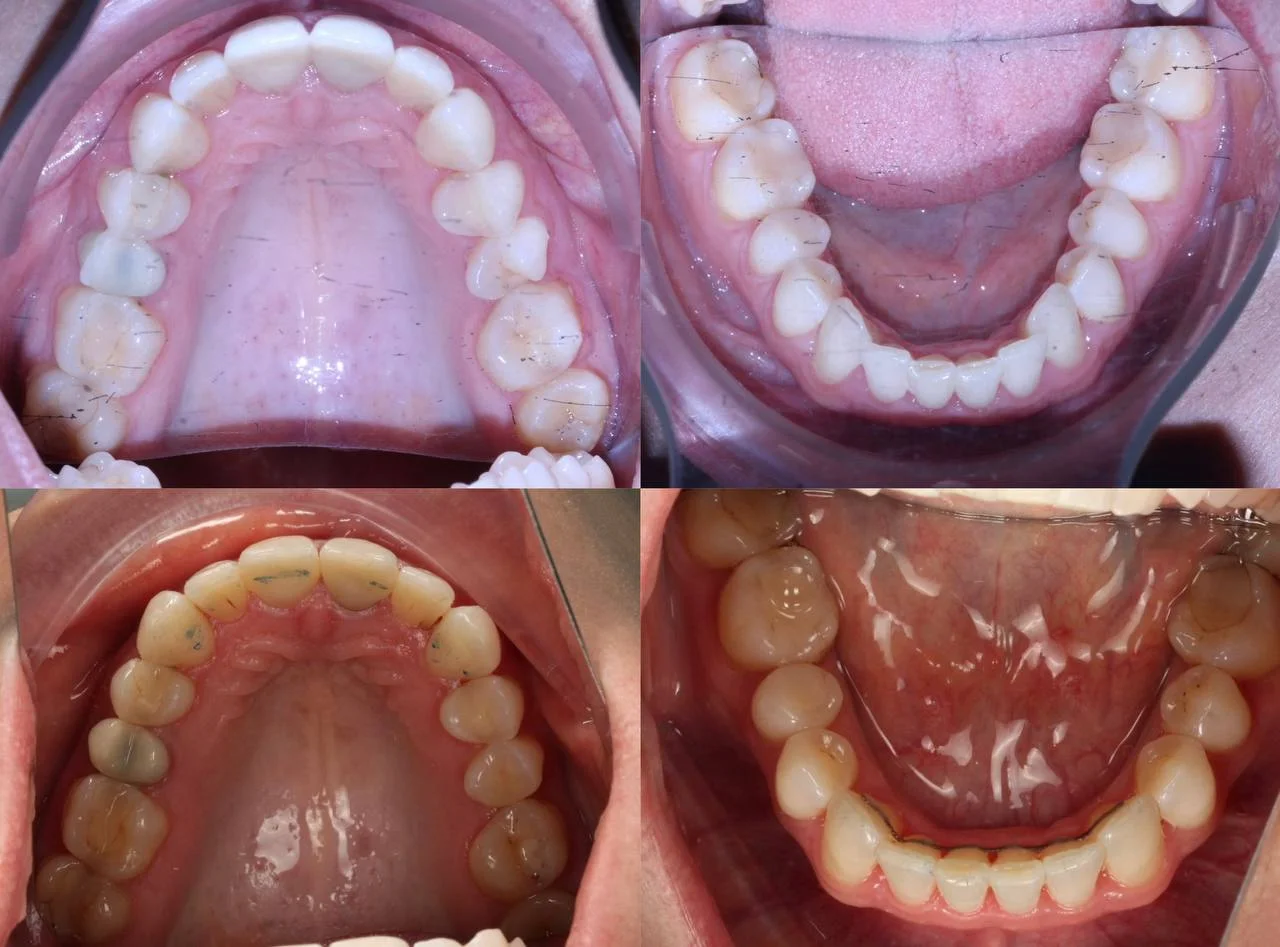

Верхняя челюсть выступала вперёд относительно нижней с обеих сторон (II класс по Энглю). Обе челюсти сужены, зубы стояли скученно. Нарушена кривая смыкания — жевательные зубы были на разной высоте. На двух передних зубах верхней челюсти ранее установлены металлокерамические коронки.

Проблема: Пациентку беспокоили неровные зубы и неправильный прикус. При осмотре нашли сразу несколько проблем: обе челюсти сужены, зубы стоят скученно, верхняя челюсть выступает вперёд (II класс по Энглю), кривая смыкания деформирована — жевательные зубы на разной высоте. На двух передних зубах верхней челюсти стояли старые металлокерамические коронки, которые нужно было учитывать при планировании.